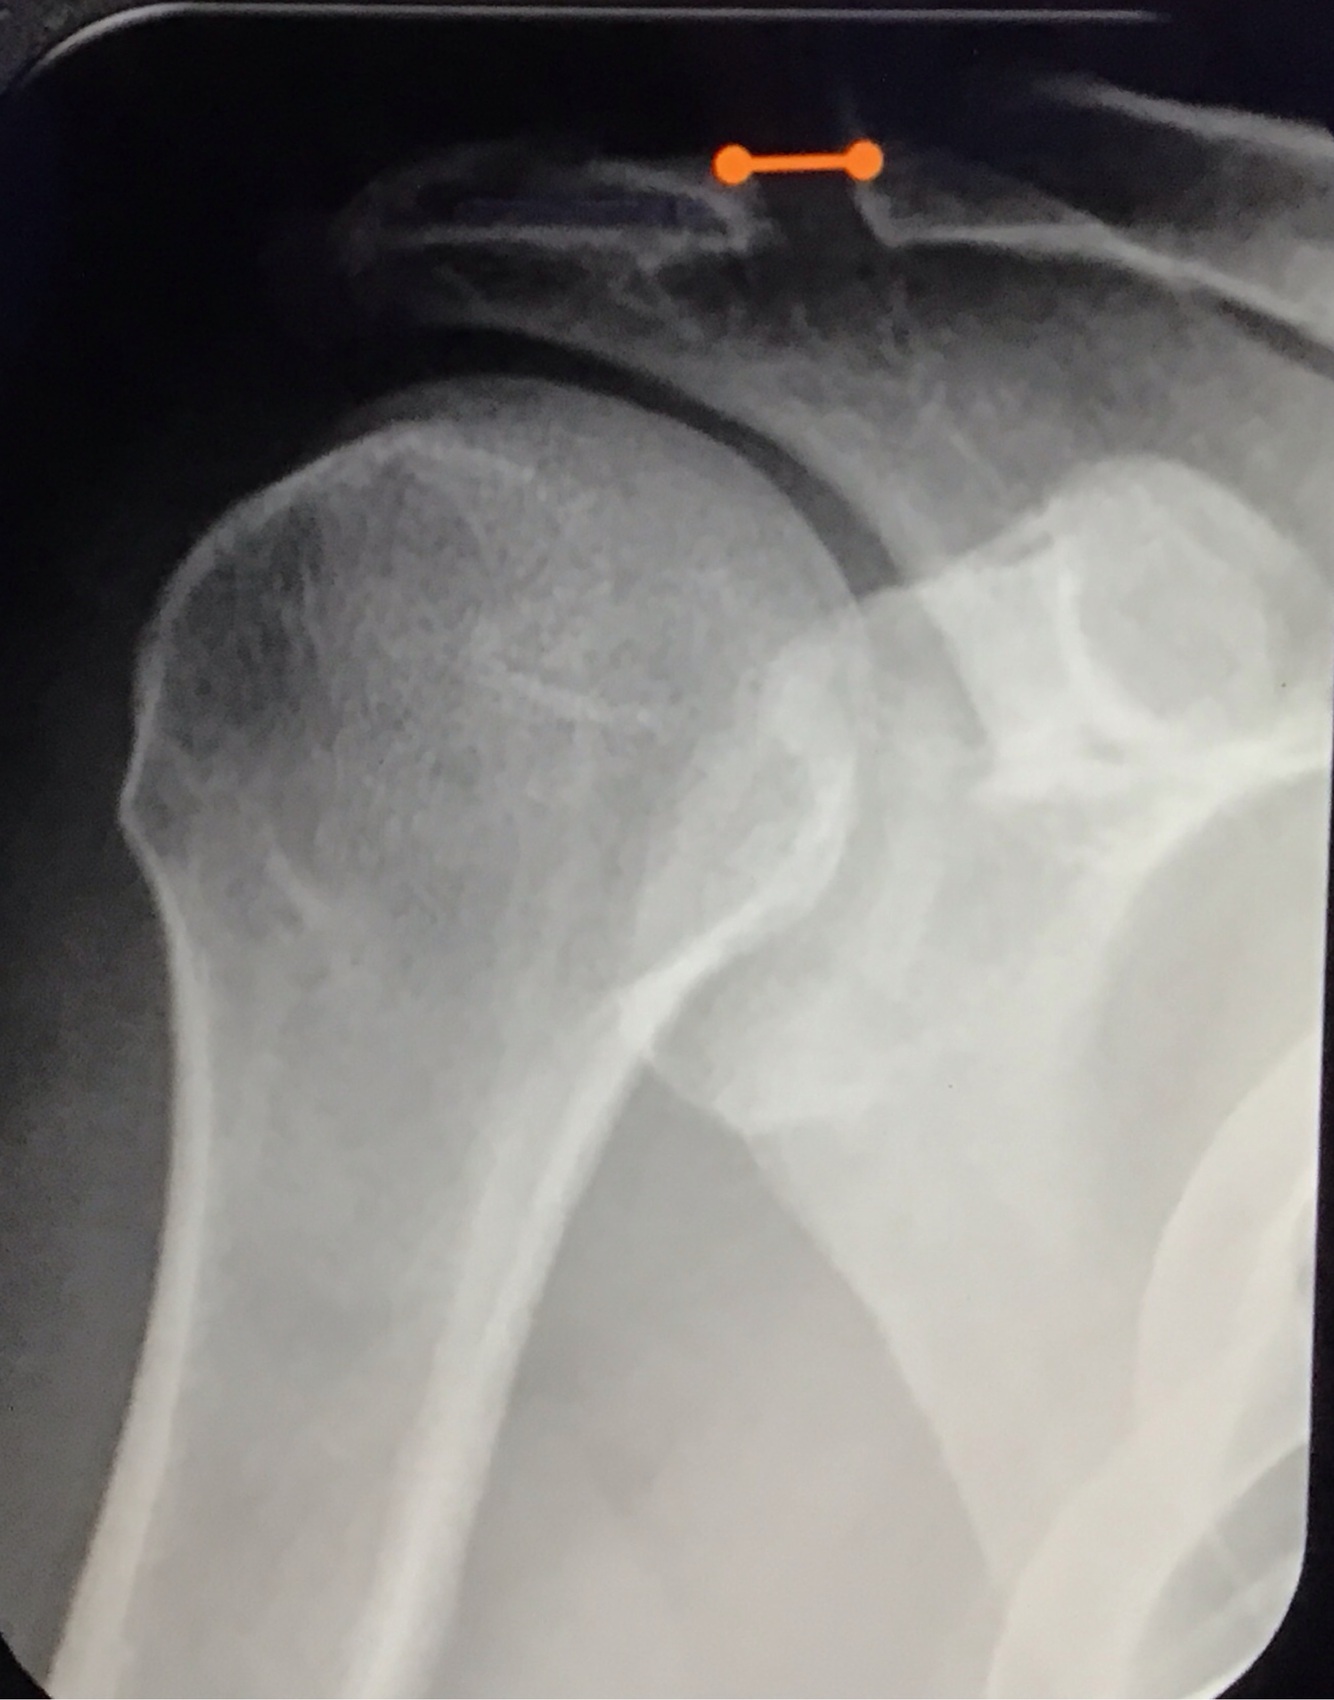

Qual a melhor incidência radiográfica pra avaliar LAC?

A

Zanca

angulação cranial de 10 a 15°

Qual a distância coracoclavicular normal?

11 a 13mm

Qual a distância acromioclavicular normal?

7mm nos homens

8mm nas mulheres